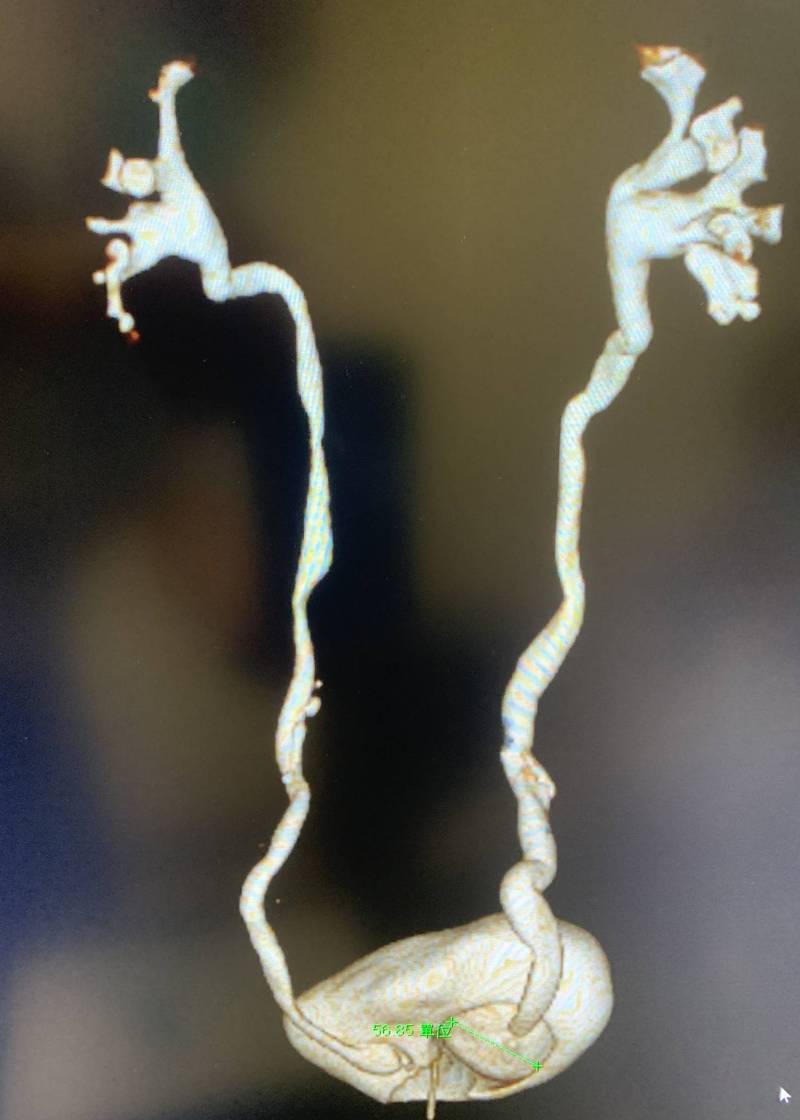

〔記者方志賢/高雄報導〕高雄一名67歲婦女,2年多前有一腫塊從尿道口突出,她靠自己把它塞回去,最近腫塊愈變愈大,怎麼用力也推不回去,嚇得趕緊就醫,醫師發現她的輸尿管長了5公分的囊腫,並從不到1公分寬的尿道口跑出來,尿液從腎臟經膨出的輸尿管,再繞回體內膀胱,儲滿後由尿道排出體外,過程「九彎十八拐」,也因此造成漏尿及解尿不順等問題。

這名婦人生產過四胎,她的輸尿管末端與膀胱交接處長了一個囊腫(囊狀膨出),膨出的大小約0.5公分至5公分,由於尿液時多時少,尿液少的時候,囊腫較小就從1公分寬尿道口膨出,後來尿液把囊腫空間繼續充填,囊腫愈變愈大,無法從尿道口縮回去,膨出在尿道口外,導致膀胱、尿道曲折不順暢,以及膀胱出口阻塞,而造成尿意滯留等問題。

沈元琦表示,輸尿管囊腫從尿道口外翻脫垂從外觀不易辨認,若沒有正確診斷,很容易誤以為是膀胱或子宮脫垂,經電腦斷層檢查才診斷出是輸尿管囊腫從尿道口外翻脫垂的罕見案例。